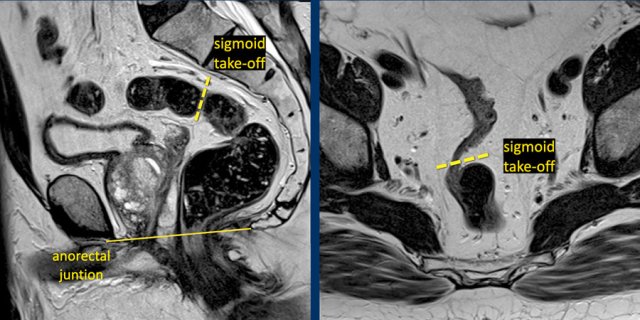

In 2019 an international consensus panel agreed on the “sigmoid take-off” as the preferred landmark to define the rectosigmoid junction and separate the rectum from the sigmoid on imaging (ref).

The sigmoid take off can be recognized on sagittal MRI as the point from which the sigmoid sweeps horizontally away from the sacrum.

The sigmoid take-off can be recognized on sagittal MRI as the point from which the sigmoid sweeps horizontally away from the sacrum and on an axial view as the point from which the sigmoid projects ventrally (figure).

Though recognizing the sigmoid take-off on imaging may be challenging in some cases due to anatomical variations between patients or varying sequence angulation, it is overall an intuitive landmark.

Tumors above the level of the rectosigmoid junction with a lower border starting proximal to the sigmoid take-off are considered sigmoid tumors.

Tumor height

The

anorectal junction marks the transition between the anal canal and

distal rectum.

It is situated at the level of the anorectal angle, which is

caused by contraction of the puborectalis muscle.

On sagittal MRI the anorectal

junction is typically situated at the level of an imaginary line between the

lower margin of the sacral bone and pubic bone.

A common approach to determine the height of rectal tumors is to measure the distance between the lower margin of the tumor and the anorectal junction, or alternatively the distance from the anal verge, which is the transition between the anal epithelium and perianal skin.